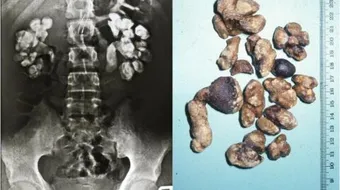

حصى الحالب هي عبارة عن أجسام صغيرة وصلبة تتشكل وتتجمع في الحالب أو المثانة البولية ، الأمر الذي يؤدي إلى حدوث مشاكل في عملية التبول إضافة إلى الشعور بآلام في تلك المنطقة ، ولا يمكن تحديد حجمها ، حيث أنها تتفاوت في الحجم من شخص لآخر ، ولكن هي صغيرة جداً لدرجة أنها لا ترى بالعين المجردة ، وتتكون عند الرجال بنسبة أكبر من عند النساء ، وهي عبارة عن ترسبات للأملاح الموجودة في الجسم ، وتكون نتيجتها تجمع هذه الترسبات في منطقة المثانة أو الحالب ، وتكون متحجرة في الغالب الأمر الذي يؤدي إلى صعوبة التلخص منها بالطرق العادية ، ويلجأ البعض إلى تفتيها من خلال استخدام الليزر أو غيرها من التقنيات، قد يخرج بعض من هذه الحصى مع البول عن طريق القناة البولية من الجسم ، ولكن هذا الأمر يكون مع القطع الصغير جداً ، كما أن صاحبها سيعاني من آلام كبيرة في المثانة أثناء عملية التبول ، هناك حالات معينة يقوم الطبيب فيها بإدخال أنبوب إلى داخل قناة البول من أجل تفتيت الحصى ، ولكن الطريقة الأكثر استعمالاً هي استخدام تقنية الليزر من أجل هذا الأمر ، حيث أنها آمنة أكثر ، كما أنها لا تسبب آلام مثل طريقة الأنبوب .

يعاني مرضى الحصى من آلام كبيرة جداً خاصة عند مرور الحصى بالحالب ، وحيث أن الحصوات كلها تنتقل إلى الحالب وتستقر فيه ، وكما أن بعض من هذه الحصى تستمر في النمو ، ويزداد حجمها يوماً بعد يوم ، ومثل هذه الحصى يلجأ الأطباء إلى تفتيها بأسرع وقت حيث أن هذه الحصى تسبب تجرح في المنطقة التي تقع فيها ، كما أن أصحاب الحصى يعانون من حرقة شديدة جداً أثناء التبول ، كما أنهم يعانون من تكرار التبول بصورة غير طبيعية ، كما أن الحصى أمر مخيف قد يعاود الرجوع ، حيث أن تفتيت الحصى لا يضمن الشفاء التام 100% ، لذلك يلجأ بعض الأطباء إلى زراعة عضو جديد في المنطقة ليمنع تكون الحصى ويتفتتها بشكل فوري يضمن عدم تكونها .